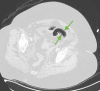

The prothrombotic nature of severe acute respiratory syndrome coronavirus 2 (SARS-CoV-2) has been well-established since the start of the global coronavirus disease 2019 (COVID-19) pandemic. Mesenteric artery thrombosis and acute mesenteric ischemia are, on their own, rare occurrences and often present with fatal gastrointestinal (GI) pathologies requiring quick identification and intervention by the clinician to improve clinical outcomes. SARS-CoV-2 infection can present with acute GI pathologies and warrants further investigation regarding anticoagulation therapy in COVID-19 positive patients. We report on a 64-year-old woman infected with SARS-CoV-2 who presented with superior mesenteric artery thrombosis and acute intestinal ischemia.